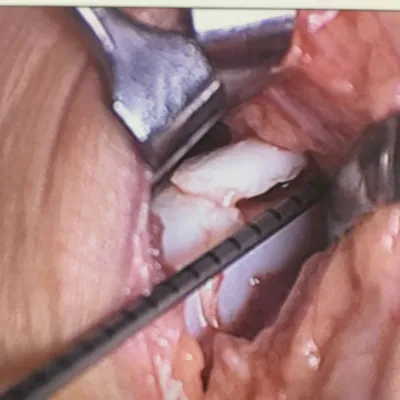

Intraop series of pics of a large osteochondral fracture on the shoulder of the talus in a teenage soccer player.

The osteochondral fracture can be seen and it is loose. We are measuring the size on the last 2 pics.

Intraop arthroscopic pics of talar OCD surgery.